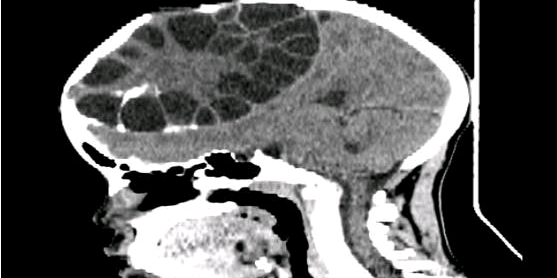

这是我从丁香园发现的,转发给各位老师共同学习

脑肿瘤-胶质瘤

脑肿瘤-脑膜瘤

小儿-儿童肿瘤

神经内科-神经内科

努力学English 昨天22:49 28阅读 0评论 0点赞